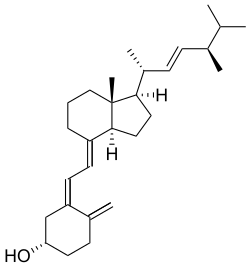

| Name | Chemical composition | Structure |

|---|---|---|

| Vitamin D1 | Mixture of molecular compounds of ergocalciferol with lumisterol, 1:1 |   |

| Vitamin D2 | ergocalciferol (made from ergosterol) |

|

| Vitamin D3 | cholecalciferol

(made from 7-dehydrocholesterol in the skin). |

|

| Vitamin D4 | 22-dihydroergocalciferol |

|

| Vitamin D5 | sitocalciferol

(made from 7-dehydrositosterol) |

|

Several forms (vitamers) of vitamin D exist, with the two major forms being vitamin D2 or ergocalciferol, and vitamin D3 or cholecalciferol.[1] The common-use term "vitamin D" refers to both D2 and D3, which were chemically characterized, respectively, in 1931 and 1935. Vitamin D3 was shown to result from the ultraviolet irradiation of 7-dehydrocholesterol. Although a chemical nomenclature for vitamin D forms was recommended in 1981,[13] alternative names remain commonly used.[3]

Chemically, the various forms of vitamin D are secosteroids, meaning that one of the bonds in the steroid rings is broken.[14] The structural difference between vitamin D2 and vitamin D3 lies in the side chain: vitamin D2 has a double bond between carbons 22 and 23, and a methyl group on carbon 24. Vitamin D analogues have also been synthesized.[3]